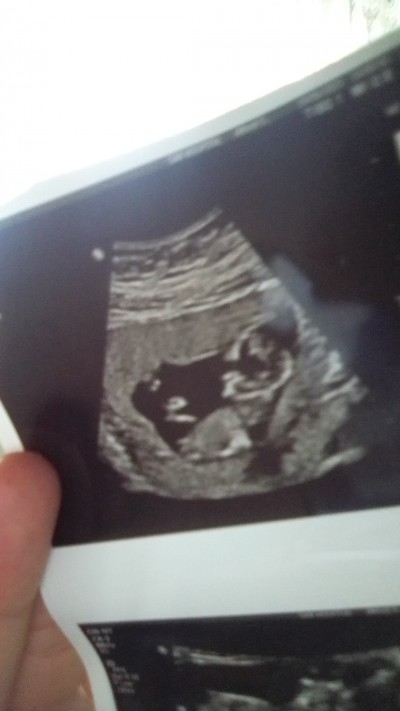

Nub teorisini bilen arkadaşların

Bebeğimin cinsiyeti nedir sizce

12+3

Kız canım benimde böyleydi minik kızım:))

Allah bağışlasın inşallah benimkide kızdır ama hep erkek hissediyorum

İnanır mısın bende öyleydim %100 erkek, bi ihtimal bile kız hissetmedim :)) doktor söylüyor yok hocam dedim erkektir o bi daha bakın:D

Nuba gore kiz gibi gorunuyor cnm